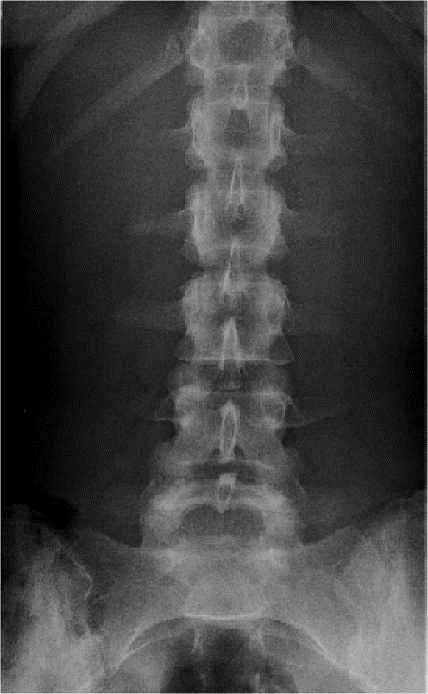

FACE

– – Le patient est en position rectitude de face

– – Il est en antéro-postérieur

– – Le dos contre la plaque

– – Il est déchaussé, les talons contre le plan de la table

– – Il est debout

– – Le plan sagittal médian est perpendiculaire au

RAYON DIRECTEUR

– – Il est centré sur L3

CRITERES DE REUSSITE

– – On doit voir les 5 vertèbres

– – Les apophyses épineuses doivent être alignées

– – Les articulation inter-vertébrales doivent être bien enfilées

ANATOMIE RADIOLOGIQUE

- – Articulaire supérieure

- – Pédicule

- – Apophyse transverse

- – Articulaire inférieure

- – Epineuse

- – Bord postérieur du canal rachidien

- – Bord supérieur des lames

- – Bord inférieur des lames

- – Isthme

- – Trou de conjugaison

- – Disque inter-vertébral

IMAGE NORMALE